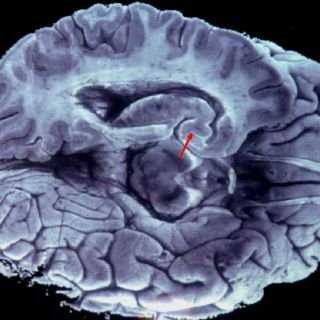

Tener un cerebro grande podría ser una desventaja, afirma el profesor Eric Abelson, del departamento de biología de la Universidad de Stanford, Estados Unidos.

Este investigador calculó la talla del cerebro de mil 679 animales (de 160 especies diferentes) y comparó estas medidas con los datos de la Unión internacional para la conservación de la naturaleza, que evalúa el riesgo de extinción de miles de especies y subespecies.

Así, puso en evidencia una correlación entre el cociente de encefalización (que mide la talla del cerebro en relación al resto del cuerpo) y el riesgo de extinción.

Esta correlación es aún más grande en los animales pequeños, afirma.

En efecto, mantener un cerebro grande tiene un coste metabólico significativo. Implica un consumo de energía más importante sin que, al parecer, esto implique mayores capacidades de adaptación.

Y para Eric Abelson, los costes de un fuerte cociente de encefalización superan las ventajas en las especies pequeñas